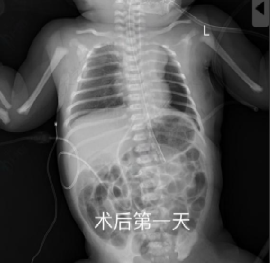

生后24小时,患儿病情逐渐趋于稳定,但影像学提示脾脏、肠管仍大量疝入胸腔,肺组织明显压缩,有可能发生肠绞窄或感染性休克,危及患儿生命。经综合评估后,依据胎儿先天性膈疝临床管理指南(2022),儿外科团队决定实施胸腔镜下膈疝修补术[2]。手术过程中可见脾脏及肠管几乎占据整个胸腔,造成肺组织严重受压。与传统开胸手术相比,胸腔镜具有创伤小、恢复快的优势,但在新生儿中操作空间极为有限,脏器质地柔嫩,手术风险和技术要求显著提高。尤其新生儿脾脏组织异常脆弱,稍微牵拉或触碰即可导致出血,且止血困难,因此操作需慎之又慎。再充分暴露后,曹主任小心翼翼地将腹腔脏器全部还纳后,随后对膈肌缺损进行修补,每一针都精准缝合,避免出现缝隙导致再次疝入,然而,由于缺损面积巨大,无法直接采用折叠缝合方式关闭,因此使用生物补片行加固修补。在麻醉科和手术部护理团队的精密配合下,儿外科团队成功将脏器还纳腹腔并精准修补膈肌缺损,手术顺利完成。术后患儿肺扩张逐渐恢复,呼吸功能改善,成功撤离呼吸机。目前状态良好,已顺利出院。